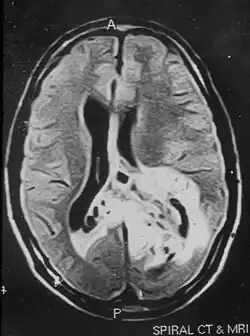

Due to the large range of causes that lead to micropsia, diagnosis varies among cases. Computed tomography (CT) and magnetic resonance imaging (MRI) may find lesions and hypodense areas in the temporal and occipital lobes.[4] MRI and CT techniques are able to rule out lesions as the cause for micropsia, but are not sufficient to diagnose the most common causes.

Non-contrast magnetic resonance imaging showing hyper-intense lesion involving the left temporal and parieto-occipital regions. The tumor is crossing the midline to the right parietal region.

An MRI image of a brain tumor occupying the left temporal and parieto-occipital regions of the brain.